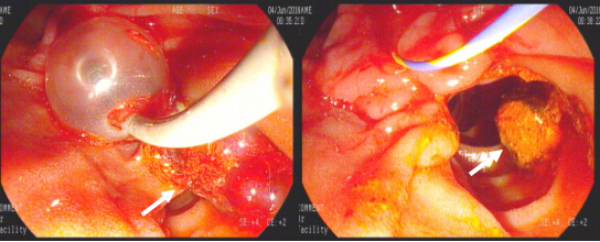

2016年7月13日,由赵刚主治医师操作,在左爱丽护士长、李婵护士、杨龙宝博士的协助下,在密切监护患者生命体征的同时对其实施ERCP手术。术中可见患者十二指肠降部有多发巨大憩室,十二指肠乳头位于其中一憩室内,属于憩室内乳头的情况,操作稍有不慎即可能引起十二指肠穿孔。一次性顺利插管至胆总管并造影,确认了胆管中结石的大小约1.2cmx1.4cm,位于肝总管处(结石可能由于插管及造影发生了位移),同时也发现由于憩室的压迫,患者胆管走形异常扭曲。我们对该患者的十二指肠乳头进行了小切开并以1.2cm胆管扩张球囊进行扩张,后以取石球囊顺利自胆管中取出巨大成型结石一枚,再次造影胆管内未见残存结石,遂置入鼻胆管,整个操作过程用时仅30分钟。患者术后第2天即恢复正常饮食,腹痛症状基本消失,目前已经顺利出院。

取石气囊取出巨大成型结石1枚(白箭头所示)